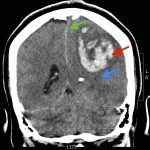

The patient’s head CT showed a significant area of hyperdensity consistent with an intracranial hemorrhage located within the left frontal parietal lobe (red arrow). Additionally, there is rightward midline shift up to 1.1cm (green arrow) and entrapment of the right lateral ventricle (blue arrow).